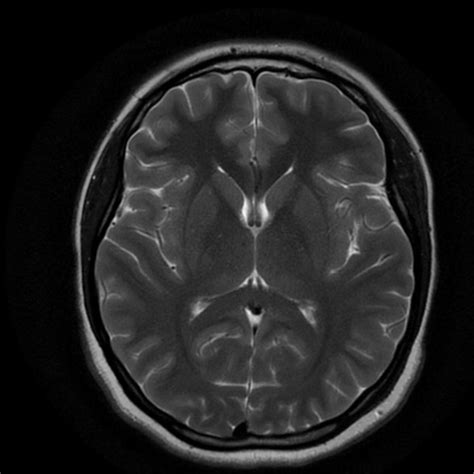

Understanding the intricacies of a Brain MRI Cage involves delving into the world of medical imaging, particularly magnetic resonance imaging (MRI). MRI is a powerful diagnostic tool that uses magnetic fields and radio waves to produce detailed images of the body's internal structures. When it comes to the brain, MRI scans are invaluable for diagnosing a wide range of conditions, from tumors and strokes to neurological disorders.

Interpreting Brain MRI Results

Once the scan is complete, the images are sent to a radiologist for interpretation. The radiologist will look for any abnormalities or signs of disease. The results are then shared with the referring physician, who will discuss them with the patient.

Brain MRI results can reveal a wide range of conditions, including:

• Tumors: Both benign and malignant tumors can be detected and their size and location determined.

• Strokes: MRI can show areas of the brain that have been damaged by a stroke.

• Neurological Disorders: Conditions such as multiple sclerosis, Alzheimer's disease, and Parkinson's disease can be diagnosed or monitored.

• Infections: Infections such as meningitis or encephalitis can be identified.

• Traumatic Injuries: Injuries from accidents or falls can be assessed.